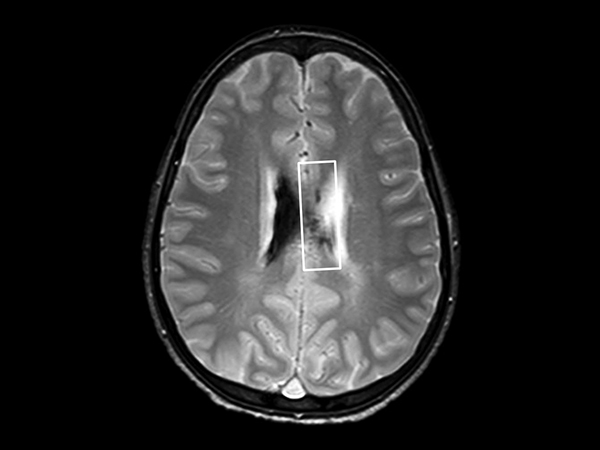

In this case, a 10-year-old girl thrown from a horse. The SWIp images provided increased visibility of the corpus callosum injury compared to the T2-weighted, diffusion weighted and gradient echo images, see the box in the images. SWIp also provides increased visibility of the cortical contusion (arrows) compared to gradient echo imaging. In this case, SWIp helped to characterize the extent of the patient’s injury, which is important to know for short term care and longer term prognosis and rehabilitation.

Axial T2w FFE